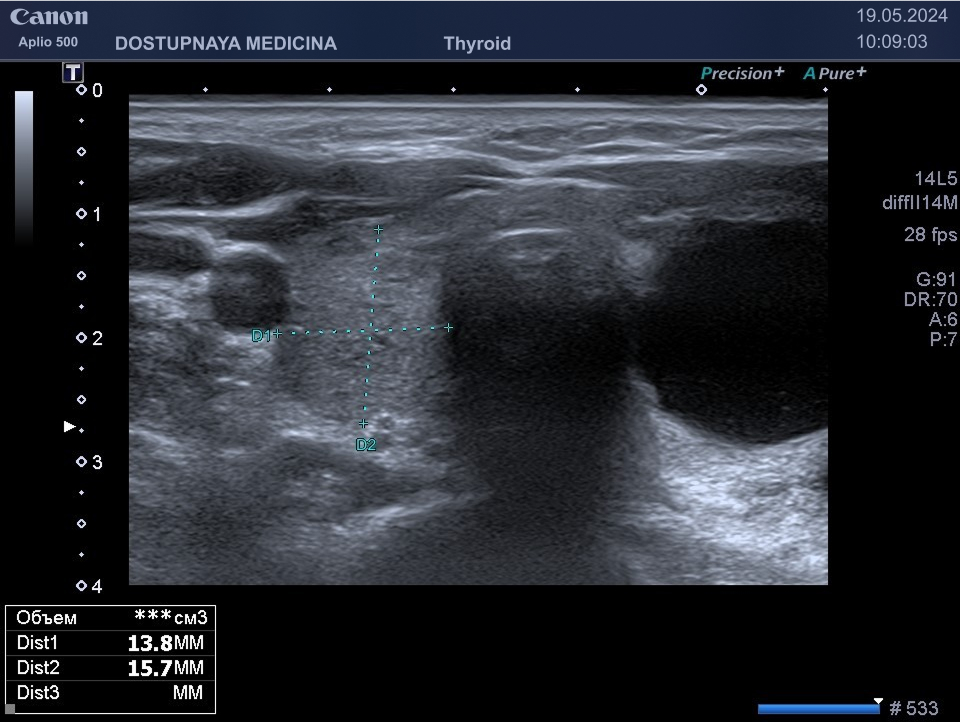

В ультразвуковой диагностике существует классификация образований щитовидной желзы по TIRADS, которая по различным критериям определяет степень онкоопастности того или ионого узла. При оценке учитывается эхоструткура образования ( кистозная, губчатая, солидная или солидно-кистозная), эхогенность ( анэхогенное, гиперэхогенное, гипоэхогенное), пространственная ориентация горизонтальная, вертикальная, неопределённая), контуры образования (ровные, дольчатые, зазубренные с острыми углами), наличие эхогенных включений( макрокальцинаты, микрокальцинаты, периферическая кольцевидная кальцификация). В зависимости от этих критериев выделяют различные категориии объёмных образований в щитовидной железе:

TIRADS 3 – низко подозрительное образование, требующие динамическое наблюдение и тонкоигольной биопсии при размерах узла больше 2.5 см.

TIRADS 4 – умеренно подозрительное образование, требующие динамическое наблюдение и тонкоигольной биопсии при размерах узла больше 1.5 см.

TIRADS 5 – высоко подозрительное образование, требующие динамическое наблюдение и тонкоигольной биопсии при размерах узла больше 1 см.

Большинство узловых образований в щитовидной железе не нуждаются в лечении и требуют лишь наблюдения путём повторного ультразвуковых исследований.

При подозрении на озлокачествление и увеличении узла в размерах требуется тонкоигольная пункционная биопсия с полседующим цитологическим исследованием, полученного материала.